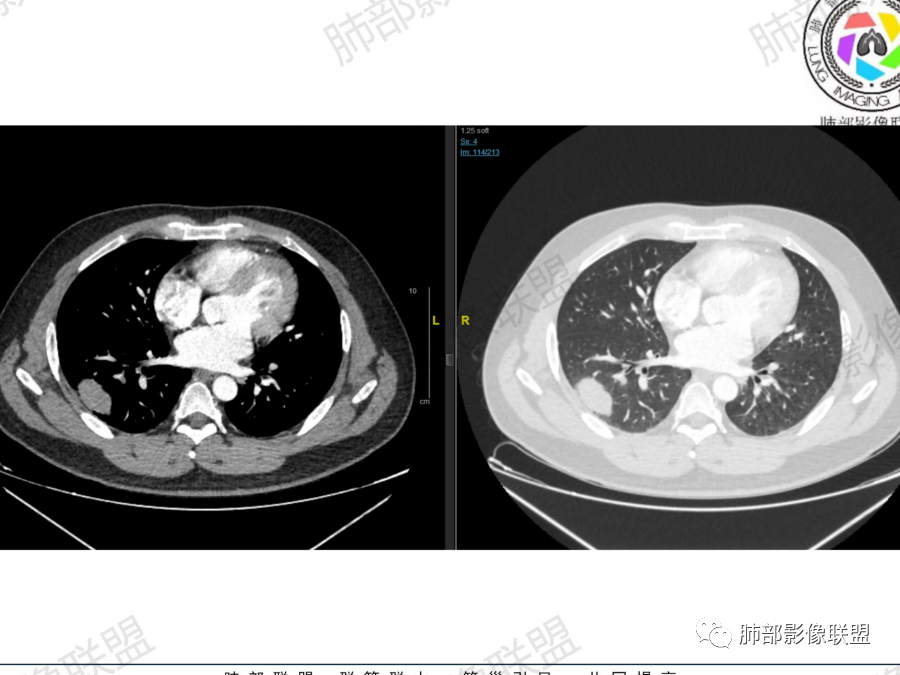

主要征象:右肺多发病变  一元论?二元论?

1.右上肺团块:分叶,不均性强化,其内支气管走行自然,增强血管影可见、清晰。

疑问:空洞还是残余肺组织?

2.右下肺结节、实变:胸膜下,长轴平行胸膜。部分似有晕影。支气管进入后近段截断

2、右肺多发结节影,大者位于右肺上叶尖段,内可见空洞,空洞内壁欠规整,内可见分隔,余结节位于胸膜下、结节大小不等、形态相近,强化均匀,内部可见血管穿行,血管及支气管走行自然。结合临床及影像,符合隐球病。